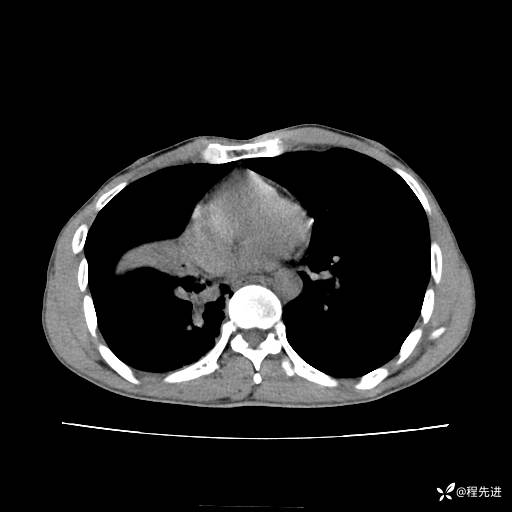

患者性别:男

患者年龄:49岁

主诉:咳嗽、胸痛1周

简要病史:1周前受凉感冒后开始出现咳嗽症状,阵发性连声咳,痰多,黄白痰,不易咳出,伴胸痛、气紧、胸闷,右侧为主,活动用力、呼吸时胸痛明显,曾在当地诊所贴敷膏药仍疼痛

体格检查:T:36.3 ℃ P:80 次/分 R:20 次/分 BP:120/88 mmHg,指脉氧饱和度97%,意识清晰,呼吸平稳,右侧第二、三肋骨压痛,可见膏药贴敷,皮肤无异常,双肺呼吸音粗,未闻及干湿性啰音。心率80次/分,节律整齐,无杂音。腹平软,全腹无压痛无反跳痛

临床诊断:社区获得性肺炎

CT平扫: